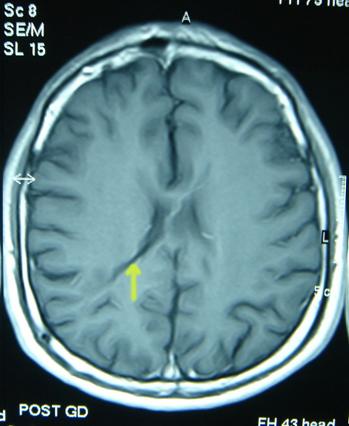

Aşırı drenaj (boşaltım) problemi olduğunda, hastalar özellikle ayakta iken şiddetlenen baş ağrısından şikâyetçidirler. Hasta yatar duruma geçince rahatlama görülür. Ameliyat öncesi beyin karıncıkları çok genişlemiş olanlarda veya büyük çocuklarda şant takıldıktan sonra fazla çalışması halinde beyin boşlukları küçülür kafatası fazla küçülemediğinden ve beyin ile beyin zarı arasındaki boşluk artar. Bu durumda beyin yüzeyinden beyin zarına uzanan köprü toplar damarlar yırtılabilir ve sonucunda beyin zarı ile beyin dokusu arasında kanlı sıvı toplanabilir (Resim 9). Şantın fazla çalışmasını engelleyecek önlemler alınmalı veya direnci daha fazla olan şant ile değiştirilmelidir.

Resim 9: Şant sonrası beyin karıncıklarının ani küçülmesi sonucunda beyin zarı ile beyin dokusu arasında kanama oluştuğunu gösteren BT.